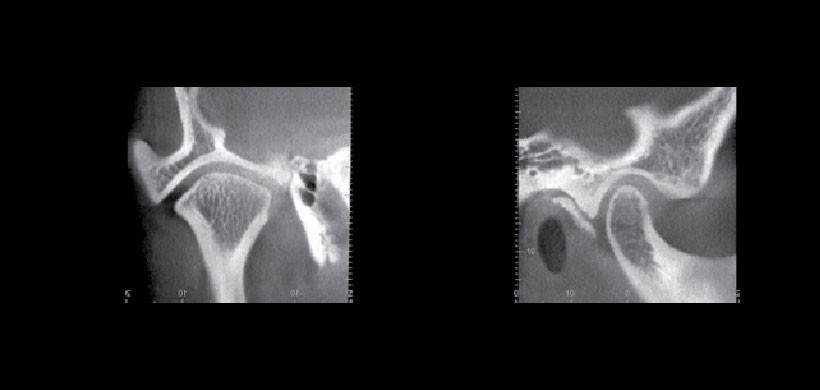

La mayor parte de los cambios morfológicos de las ATM observables en estudios tomográficos efectuados mediante la técnica cone beam, son producidos por procesos óseos degenerativos, derivados de la presencia de diversos grados de artrosis que pueden afectar esta articulación, los cuales generalmente se presentan en una secuencia que puede indicar en alguna medida, el grado de severidad del cuadro patológico. Estos son: engrosamiento de las corticales óseas articulares; y aplanamiento o facetación de las superficies óseas articulares, los primeros signos imagenológicos son considerados por muchos autores como cambios adaptativos de la ATM. A estos se le pueden agregar signos patológicos como erosiones de las corticales óseas articulares con compromiso del tejido óseo esponjoso subyacente, formación de osteofitos; presencia de “dobles corticales”; osteólisis avanzada de las superficies condilares, presencia de quistes subcondrales; y anquilosis de ATM. En muchos cuadros de artrosis de ATM estos signos imagenológicos se presentan en forma concurrente. Las alteraciones morfológicas de las ATM normalmente vienen además acompañadas de alteraciones posicionales y funcionales.